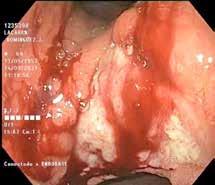

Se revisaron las pruebas solicitadas en Urgencias. En la analítica se en contró una hemoglobina (Hb) de 14 g/dl, un volumen corpuscular medio (VCM) elevado (106μ³) compatible con su historia de alcoholismo o con un déficit de ácido fólico o vitamina B12, una discreta elevación de la proteina C reactiva (13,2 mg/dl) sin elevación de otros reactantes de fase aguda y unas enzimas hepáticas dentro de la normalidad, con la aspartato transfe rasa ligeramente elevada 39 U/L (rango de normalidad: 5-34). Los tóxicos en orina fueron negativos, así como la etanolemia. La radiografía (rx) de tórax mostraba una condensación en el lóbulo superior izquierdo en posi ble relación con la infección tuberculosa diagnosticada en 2011 (Figura 1). La TC -a pesar de no mostrar signos de patología aguda intracraneal, ni masas ni signos de sangrado- sí que mostraba atrofia cerebral con surcos muy marcados, hallazgo no concordante con la edad de nuestro paciente (Imagen 2).

Figura 1. Radiografía de tórax en bipedestación AP y Lat.

Lesiones residuales/cicatriciales en campo superior izquierda, con aumento de densidad de parénquima, bronquictasias y pérdida de volumen, en relación con antecedente de TBC. Parénquima pulmonar derecho aceptablemente ventilado. Siluesta cardiovascular normal.